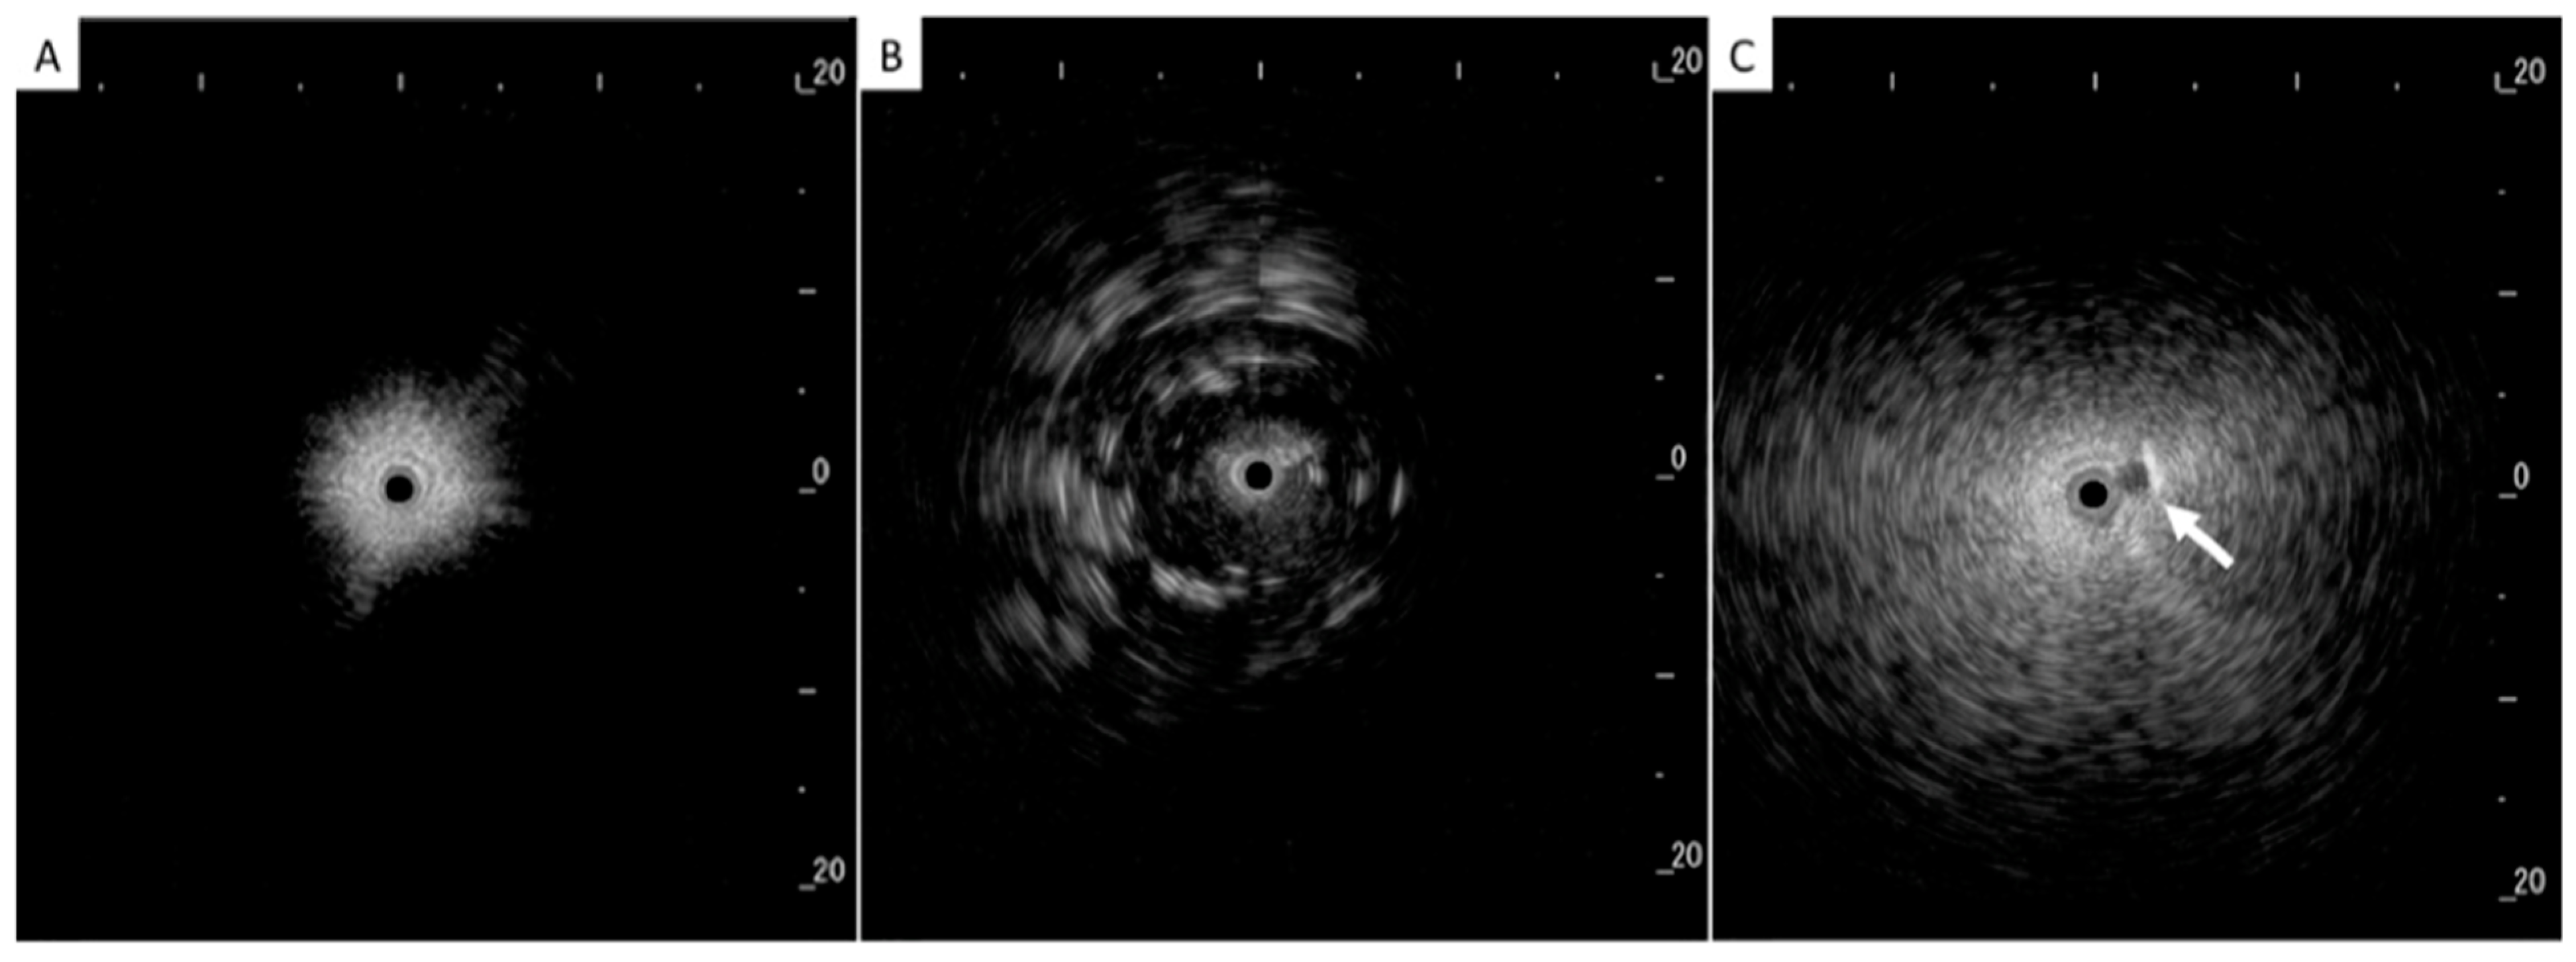

In addition to HRCT, there are several other imaging advancements very similar to the ones discussed in the lung cancer section that help in the diagnosis and monitoring of parenchymal lung diseases, including OCT, ultrasound, and PET. Earlier, we reviewed how OCT can be helpful for diagnosing lung nodules. Similarly, OCT offers minimally invasive high-resolution images for ILD diagnosis [20]. OCT has been shown to have sensitivity and specificity of 100% in detecting usual interstitial pneumonia patterns [21]. External validation and larger studies are required for clinical implementation. This could reduce reliance on surgical lung biopsy. Another form of imaging used includes ultrasound, which we have seen used for lung nodules as well. For parenchymal lung diseases, the pattern of abnormality is typically more diffuse. The radial ultrasound probe is inserted through a bronchoscope into the patient’s airways until it reaches the pleural surface. The probe is then slowly withdrawn from the pleura to the hilum, while examining the characteristics on the ultrasound image. This method helps determine a better location to biopsy. A dense sign correlates with a higher pathological confidence than a blizzard sign (Figure 3). Moreover, radial EBUS helps clinicians choose appropriate biopsy sites for cryobiopsy and identify blood vessels close to lesions, which should be avoided when a biopsy is performed. Minoru et al. demonstrated high-quality lung specimens with dense signs on radial EBUS while decreasing the bleeding risk [22]. Sarcoidosis is another common multisystemic disease characterized by the formation of non-caseating granulomas in various organ systems. Establishing the presence of inflammatory activity is crucial for diagnosis and the monitoring of treatment. One of the most common organs affected by sarcoidosis include the lungs. This condition affects the lungs in more than 90% of patients [23]. Sarcoidosis can affect the parenchyma, the mediastinal and hilar lymph nodes, or both. Increased FDG uptake in the pulmonary parenchyma is associated with inflammatory activity, presumably inflammatory cells, including activated macrophages, lymphocytes, and neutrophils, and, possibly, disease severity (Figure 4). One cannot solely rely on a PET scan for diagnosis and must use other forms of diagnosis, including history, physical examination, and serologic markers. It was found by Mostard et al. that 20% PET scans are positive without serological signs of inflammatory activity. PET can add value to the assessment of sarcoidosis and other inflammatory lung diseases in patients with symptoms despite the absence of serologic inflammatory markers [24]. Other patients do not exhibit parenchymal disease and just have mediastinal and hilar lymphadenopathy. In addition to PET scans, which can show hypermetabolic uptake in lymph nodes, ultrasound with linear EBUS can be used to examine the lymph node in real time and obtain tissue samples. Characteristics that can be examined include lymph node size, shape, margin, echogenicity, central hilar structure, and granular appearance (Figure 5). Furthermore, EBUS TBNA has shown a sensitivity of 89–100% and a specificity of 94–96% in diagnosing sarcoidosis [25]. This procedure and imaging technique can be used for diagnosing other thoracic diseases that infiltrate the mediastinal and hilar lymph nodes, such as infectious causes like TB or fungal infections, other inflammatory diseases like hypersensitivity pneumonitis and vasculitis, and malignant diseases.

Figure 3. (A) Normal lung, (B) dense sign, and (C) blizzard sign. The white arrow is a pulmonary artery. Reproduced from Inomata et al., 2020 [22]. Shared in accordance with the Creative Commons Attribution Non Commercial (CC BY-NC 4.0) license, which permits others to distribute, remix, adapt, build upon this work non-commercially, and license their derivative works on different terms, provided the original work is properly cited, appropriate credit is given, any changes made indicated, and the use is non-commercial. See: http://creativecommons.org/licenses/by-nc/4.0/.